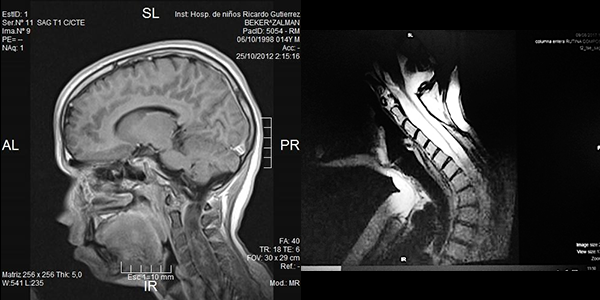

Es evidente que el límite entre el tejido medular y tumoral en las lesiones como los astrocitomas es indiscernible lo que dificulta la posibilidad de resección completa; en los tumores como los ependimomas esta diferencia es más franca y permite seguir un plano de disección seguro (Figuras 3, 4 y 5). Lo anterior condiciona nuestros resultados como han puntualizado diversos autores.5,8 El estado general previo a la cirugía requiere de una valoración juiciosa de las posibilidades de resección. Por ejemplo, el caso 12 (Figura 6) es una paciente portadora de Enfermedad de Von Hippel Lindau, Hemangioblastoma cervical biopsiado en otra institución del exterior del país, fijación de columna cervical y sindrome de Cushing por exceso de medicación corticoidea cuya cirugía debió suspenderse en dos oportunidades por la disminución de su capacidad ventilatoria. Con estos antecedentes y la delgada capa de tejido medular evidenciada intraoperatoriamente se optó por una resección subtotal. A los cuatro meses de la cirugía la paciente recuperó la marcha autónoma y demás parámetros clínicos.

Figura 3: Caso 10. Ependimoma cervical pre operatoria: Lesión sólida C3 y dilatación siringomiélica. Posoperatorio: resección completa, disminución de la cavidad. Restos hemáticos decantados.

Figura 5: Caso 1. Astrocitoma Pilocítico cervical. A: preoperatoria. B: Cifosis 2 años post resección. Marcada “atrofia” medular.

Figura 6: Caso 12. Hemangioblastoma cervical. Ocupa la mayor parte del cordón medular marcado con círculo.